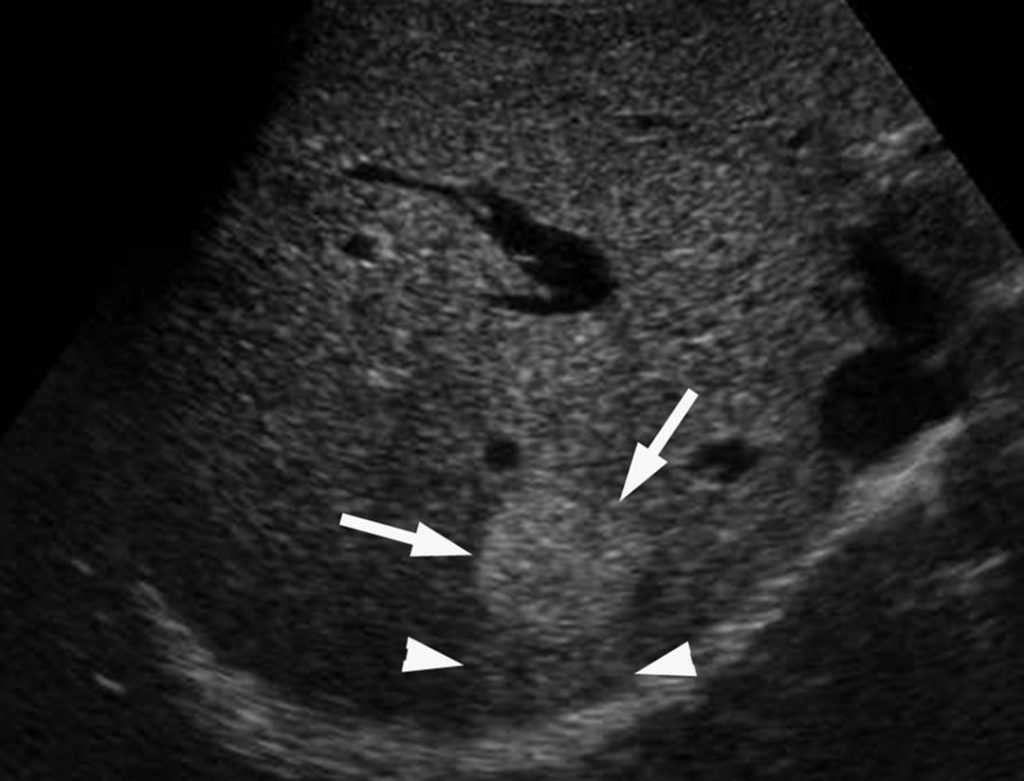

En échographie, leur aspect est variable, hypoéchogène, hyperéchogène ou mixte. Au scanner, elles sont légèrement hypodenses par rapport au foie avant injection (figure 16.6). En IRM, les lésions sont typiquement hypo-intenses en pondération T1 et hyperintenses en pondération T2.

Fig. 16.6. Coupes scanner de métastases hépatiques d’origine colorectale.

La coupe sans injection montre plusieurs lésions spontanément hypodenses (flèches) (A). Au temps portal (B), le parenchyme hépatique se rehausse beaucoup plus que les lésions, ce qui augmente son contraste avec le parenchyme hépatique adjacent.

Source : CERF, CNEBMN, 2022.

Après injection de produit de contraste au scanner ou en IRM, elles sont caractérisées par un rehaussement faible et hétérogène (plutôt en couronne périphérique) au temps artériel ou portal, ce qui les rend bien visibles sous forme de nodule(s) hypodense(s) par rapport au foie.